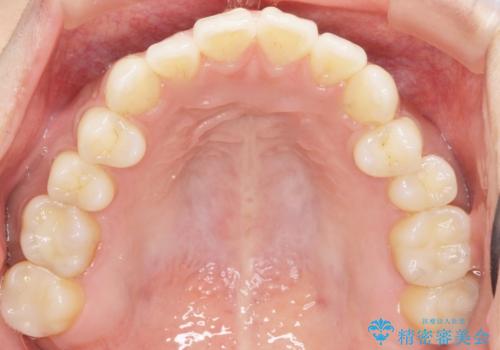

気にされていたフロスをした時のにおいがなくなり、喜んで頂けました。

治療終了後半年のメンテナンス時には「咬み合わせもばっちりです!」とおっしゃって下さいました。

インレーの種類:セラミックインレー e-max press